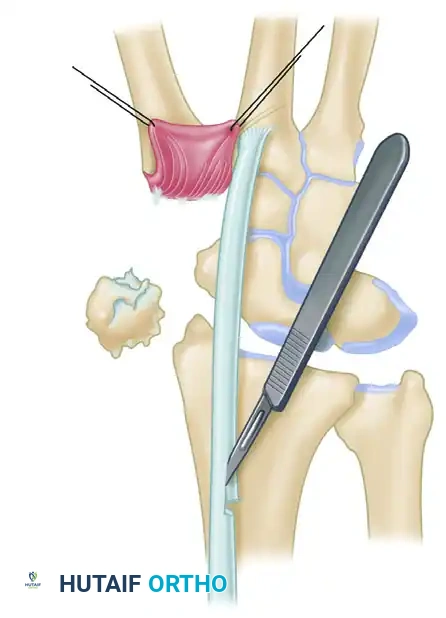

- Trapeziectomy: After exposing the joint through a volar incision along the FCR path and reflecting the thenar muscles, perform a complete excision of the trapezium. Care must be taken to protect the underlying FCR tendon during piecemeal or en bloc resection.

- Bone Tunnel Creation: Using a 4-mm rough burr, create holes through the base of the thumb metacarpal, directing them proximally and radially. Connect these holes using a series of curets (usually up to a No. 2) to form a smooth, continuous tunnel.

Figure A: Holes made in the thumb metacarpal base following trapeziectomy.

Intraoperative view of the trapezial void and preparation of the metacarpal base.